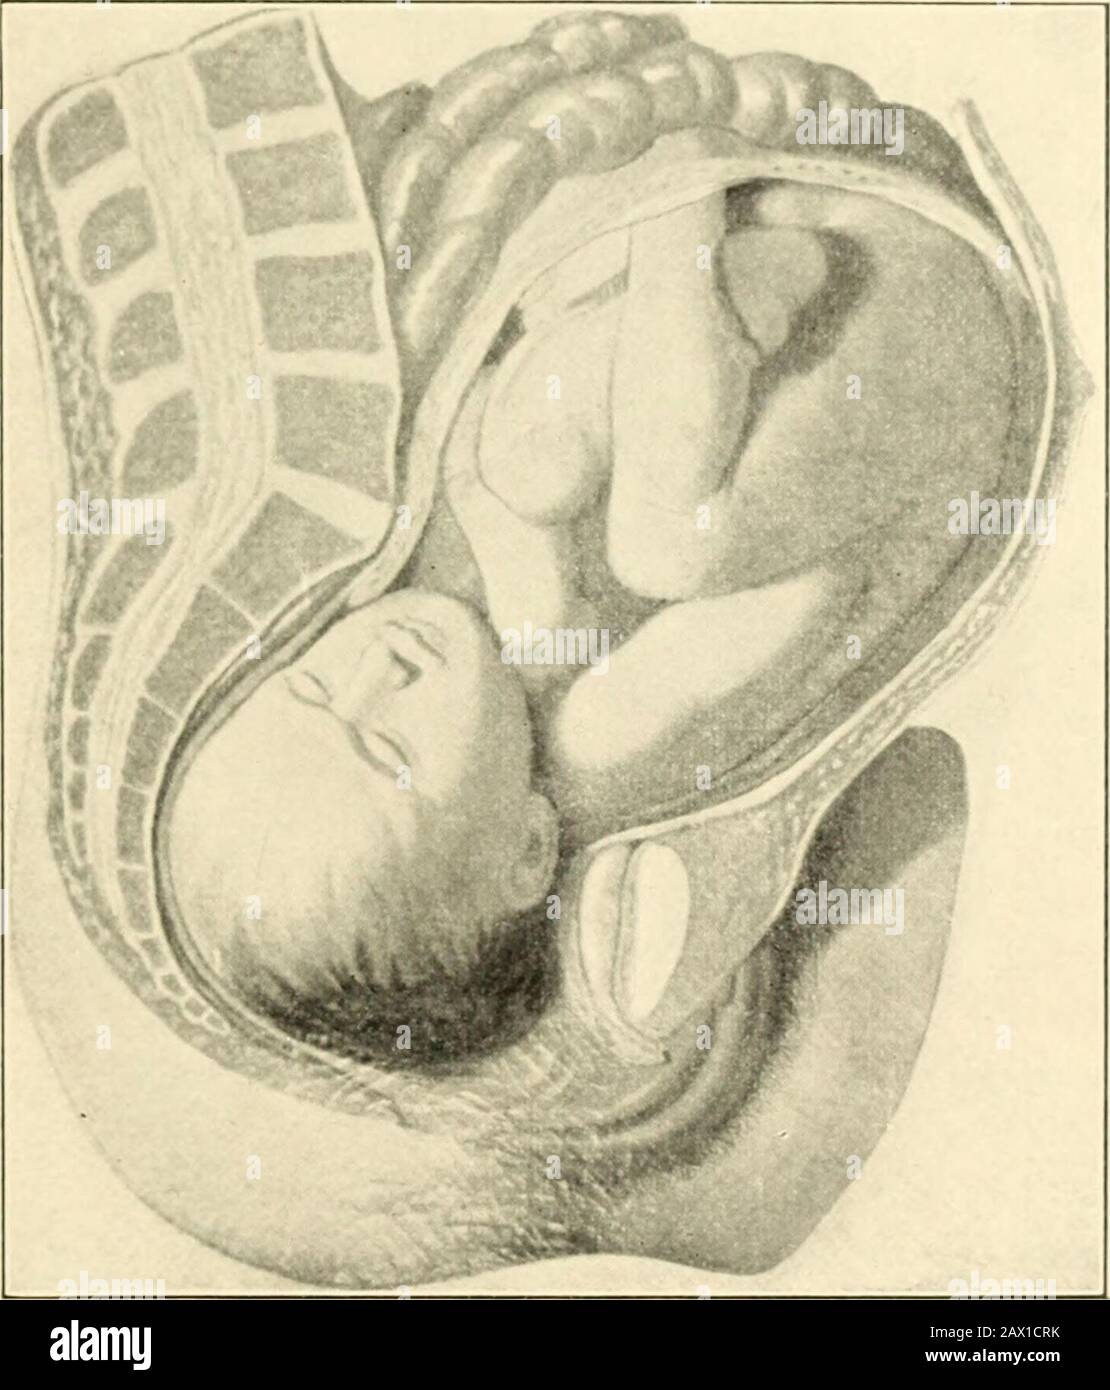

This is the two positions of an infant while in the uterus. copyright 1844 Stock Photohttps://www.alamy.com/image-license-details/?v=1https://www.alamy.com/stock-photo-this-is-the-two-positions-of-an-infant-while-in-the-uterus-copyright-37139594.html

This is the two positions of an infant while in the uterus. copyright 1844 Stock Photohttps://www.alamy.com/image-license-details/?v=1https://www.alamy.com/stock-photo-this-is-the-two-positions-of-an-infant-while-in-the-uterus-copyright-37139594.htmlRFC4BRX2–This is the two positions of an infant while in the uterus. copyright 1844